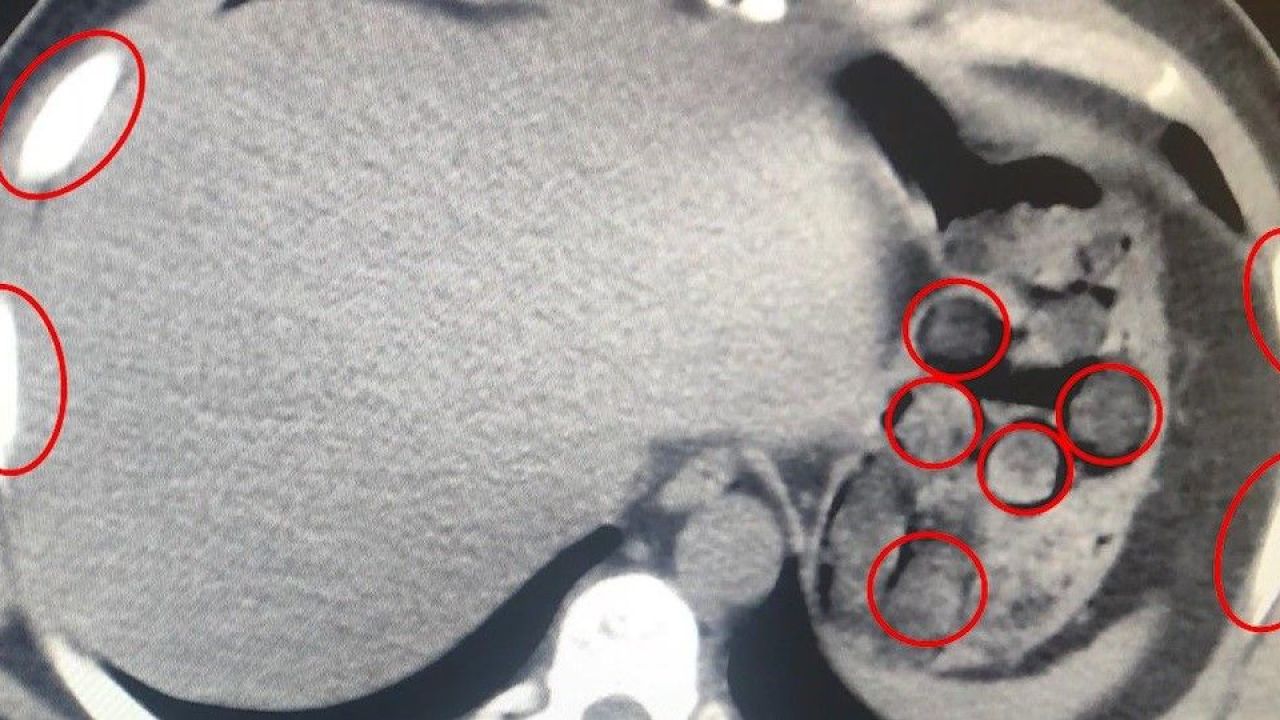

Bitlis İl Emniyet Müdürlüğü, uyuşturucu ile mücadele kapsamında gerçekleştirdiği operasyonda büyük bir sevkiyatı engelledi. Tatvan ilçesinde durdurulan bir yolcu otobüsünde seyahat eden yabancı uyruklu iki kişi, mideye gizledikleri 136 kapsül uyuşturucu maddeyle yakalandı.

Şüphelilerin sağlık kontrolleri sırasında yapılan tıbbi müdahalede, toplam 1 kilo 48 gram metamfetamin içeren 136 kapsülün yutularak taşındığı ortaya çıktı. Zanlılar, "Uyuşturucu Madde İmal ve Ticareti" suçlamasıyla gözaltına alındı. Emniyetteki işlemlerinin ardından çıkarıldıkları mahkemece tutuklanarak cezaevine gönderildi.